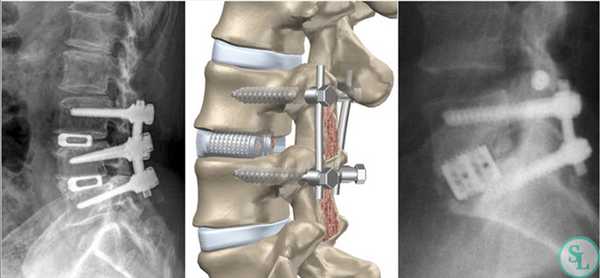

Жесткие стабилизирующие системы

Системы жесткой фиксации подразумевают установку в межпозвонковое пространство костного трансплантата (обычно взятого из подвздошной кости пациента) или специального искусственного кейджа с последующим монтажом на два и более соседних позвонка металлической конструкции. В результате они обездвиживаются и со временем сращиваются между собой, т. е. происходит спондилодез.

Метод позволяет полностью устранить сегментарную нестабильность позвоночника, но при необходимости фиксации одновременно большого количества позвонков провоцирует уменьшение возможной амплитуды движений.

Жесткая стабилизация подразумевает использование техники транспедикулярной фиксации или транскутанной стабилизации. Они очень похожи между собой и отличаются одинаковой эффективностью, но последняя обладает лучшим косметическим эффектом, поскольку все манипуляции осуществляются через точечные проколы мягких тканей.

Суть метода состоит в применении специальных титановых винтов и пластин. Винты вкручиваются в точку пересечения поперечных отростков позвонка с суставными по обеим сторонам позвонка. Таким образом, фиксируется минимум 2 позвонка, хотя в ряде ситуаций требуется стабилизация значительного большего количества позвоночно-двигательных сегментов. Через шляпки винтов пропускают титановую пластину, обеспечивающую жесткость конструкции и распределение нагрузки на нее.

На шейных уровнях применяются и стабилизирующие тактики оперативных вмешательств, каждая из которых, кстати, может идти совместно и с другими видами операций. Наиболее популярные из стабилизирующих методов:

- - неподвижное соединение (сращивание) двух или более позвонков при их нестабильности;

Если клиника симптомов не поддается консервативной терапии или неинвазивные способы не могут быть задействованными ввиду сильно прогрессирующего стеноза, назначается операция. Вмешательство предполагает использование декомпрессионной ламинэктомии под общим наркозом. При комбинированной проблеме, например, вместе с грыжей, ее сочетают с микродискэктомией и спондилодезом. При спондилодезе осуществляют скрепление смежных позвонков металлическими фиксаторами (стержнями, пластинами, крючками и пр.), установку межтеловых имплантатов или вживление костного трансплантата с металлической гильзой.

Установка металлической конструкции.

Декомпрессивно-стабилизирующая хирургия

Декомпрессивные операции иногда сочетаются с имплантацией стабилизирующей системы, если есть необходимость устранения или предупреждения нестабильности позвонков. Фиксация (стабилизация) после освобождения нервно-сосудистых образований подразумевает скрепление предрасположенных к анормальному смещению позвонков специальными конструкциями и имплантатами неподвижного или динамического типа.

Неподвижная тактика соединения - это укладка в межпозвонковое отверстие костного трансплантата или кейджа для обездвиживания и формирования спондилодеза (сращения) двух и более позвонков с последующей фиксацией стабилизированного участка титановой металлоконструкцией. Костный материал для пересадки обычно берется у пациента из гребня повздовшной кости, реже применяют аллотрансплантаты.

Техника декомпрессивной операции

Сразу отметим, что такой хирургический подход определенным образом чреват дестабилизацией ламинэктомированных костных тел. Поэтому довольно часто возникает необходимость в проведении ламинэктомии с фиксацией позвонков, то есть совместно со спондилодезом. А это означает, что по завершении основного процесса хирургии пара или несколько позвонков могут быть скреплены между собой специальной металлической пластиной, возможно, дополнительно понадобится произвести трансплантацию костной ткани, взятой у пациента из подвздовшной кости. Благодаря произведенной фиксации соединенные элементы хоть и будут обездвижены, каких-либо существенных ограничений подвижности люди, как правило, не испытывают.

- Если специалист считает необходимым провести стабилизацию позвонков, дабы воспрепятствовать формированию нестабильности, на нужный участок позвоночника устанавливают специальные опорно-стабилизирующие конструкции, вживляют трансплантаты или синтетические заменители костной ткани.